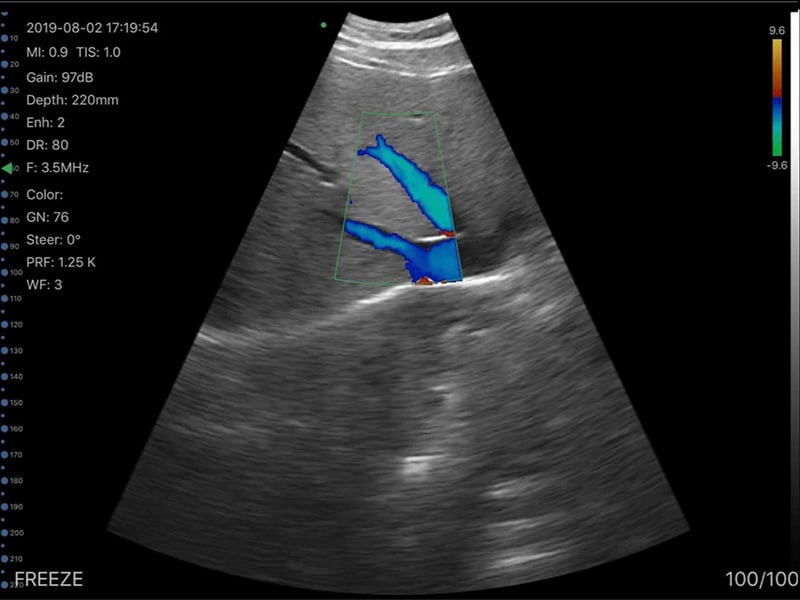

Dr. Sophia Kim used the DrSono Tri-scan Max to monitor the growth of a fetus at 28 weeks of gestation in a patient with a history of intrauterine growth restriction (IUGR). By measuring the fetal biparietal diameter (BPD), head circumference (HC), abdominal circumference (AC), and femur length (FL), she confirmed that the fetus was growing appropriately, alleviating the patient's concerns.

In addition to performing detailed biometric measurements to estimate fetal weight, Dr. Kim utilized the color Doppler mode to assess the umbilical cord blood flow, ensuring proper fetal circulation. She also conducted a thorough evaluation of the fetal spine and lateral ventricles, confirming normal development. Amniotic fluid levels and fetal movement were also checked, providing a comprehensive overview of the fetus's well-being.